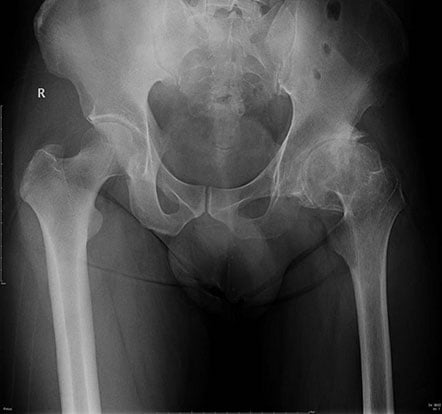

Hip osteoarthritis before surgery Hip osteoarthritis after surgery

Prior to treatment, the doctor will examine your hip condition through radiographs, CT scan or MRI to assess the degeneration severity of the hip joint.